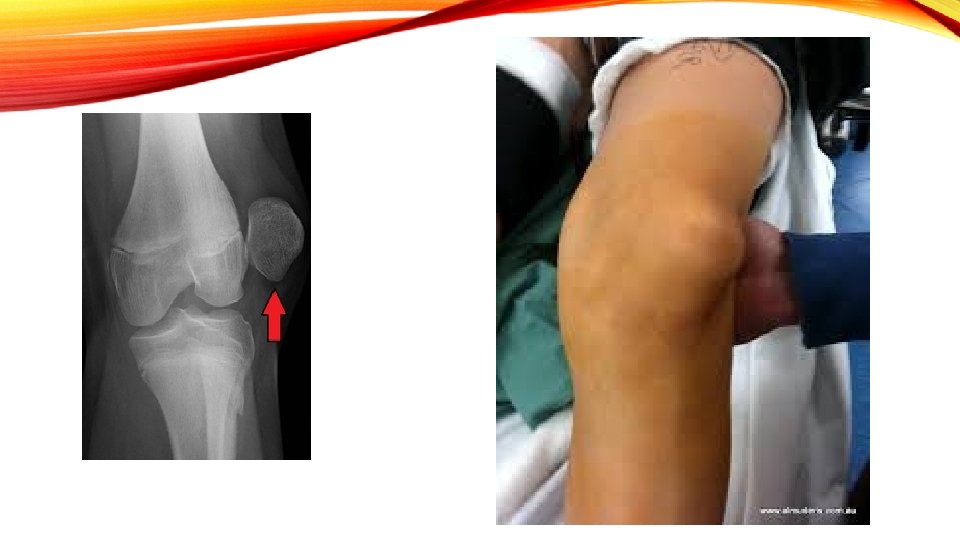

DISLOCATIONS: TIBIAL FEMORAL AND PATELLAR • Tibial Femoral: Multiple Ligaments are torn! Could be combined with a fracture; massive pain, swelling, deformity call 911! • Rare in sports • Follow-up with orthopedic specialist

PATELLA FEMORAL DISLOCATION • Medially directed valgus force similar to mechanism for ACL • i. e athlete plants, decelerates and cuts in opposite direction • End result: Vastus lateralis pulls patella laterally – patella rests on lateral femoral condyle • Special Test: Patella Apprehension • 911 call! Reduction of dislocation must take place ASAP by a physican